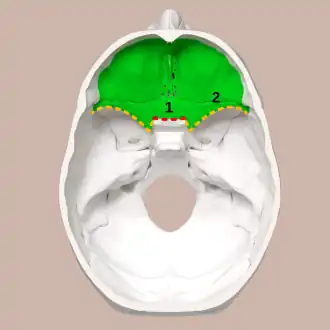

Superior view of the skull base. Anterior cranial fossa shown in green. 1: Sphenoidal limbus (anterior margin of the chiasmatic groove) | |